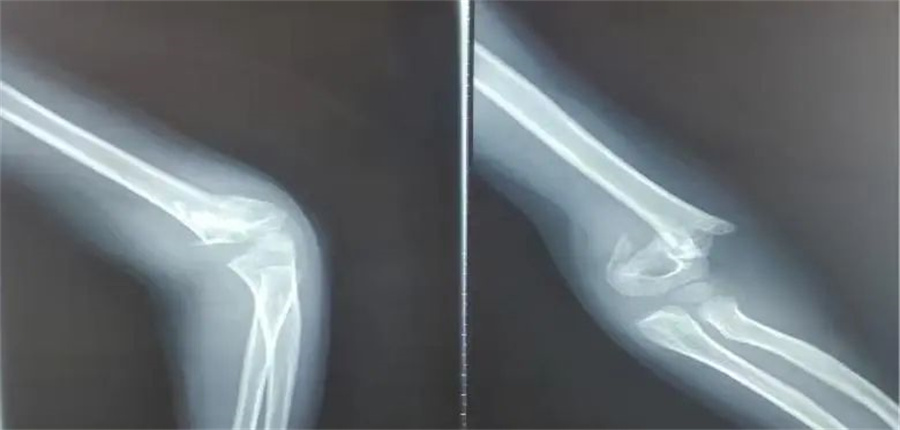

诚瑞的家长赶紧带他来到北京儿童医院集团医院·德州扑克游戏网 。入院当天,骨科医生发现,孩子是重度伸直型三度肱骨髁上骨折。

在各项检查指标都正常的情况下,儿童医院骨科的医护人员为他做了髁上骨折闭合复位术。

正常情况下,这属于常规手术。但是由于诚瑞太胖,胳膊又短又粗,复位的时候摸不到骨头,无形中增加了手术难度。

骨科医生在放射线下,一点一点摸索,最终复位成功,并且术后没有切口,没有瘢痕,4天后,孩子顺利出院。